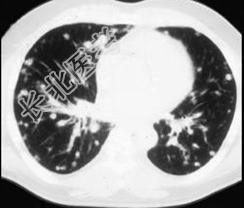

- 单项选择题女,72岁, 咳嗽,胸闷, 呼吸困难1月余,1年前行结肠癌根治术, CT检查如图,请选择最可能的诊断 ( )

B、肺转移瘤